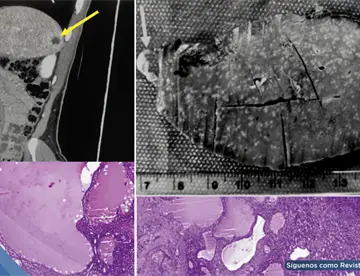

<p>La tomografía torácica y la <strong><a href='https://medicinaysaludpublica.com/tags/broncoscopia/54407' target='_blank'>broncoscopia</a></strong> confirmaron una hemorragia pulmonar secundaria a trombosis de la vena cava superior, evidenciando un diagnóstico poco frecuente que puede imitar una emergencia digestiva.</p>

<h1><strong>Evaluación inicial: Sin evidencia de <strong>sangrado</strong> digestivo activo</font></strong></h1>

<p>La endoscopia digestiva alta mostró várices esofágicas pequeñas y gastropatía erosiva, pero sin <strong>sangrado</strong> activo que justificara la gravedad del cuadro. Este hallazgo obligó a ampliar el enfoque diagnóstico, considerando causas no gastrointestinales.</p>

<p>En este contexto, la tomografía computarizada de tórax reveló un hallazgo clave: trombosis de la vena cava superior con abundante circulación colateral mediastínica. Además, se evidenciaron áreas de consolidación alveolar compatibles con hemorragia pulmonar y un derrame pleural derecho.</p>

<strong>Confirmación diagnóstica</font></strong></h2>

<p>La <strong>broncoscopia</strong> fue determinante al identificar <strong>sangrado</strong> activo en el árbol bronquial derecho con presencia de coágulos adheridos, confirmando que la fuente del <strong>sangrado</strong> era respiratoria y no digestiva.</p>